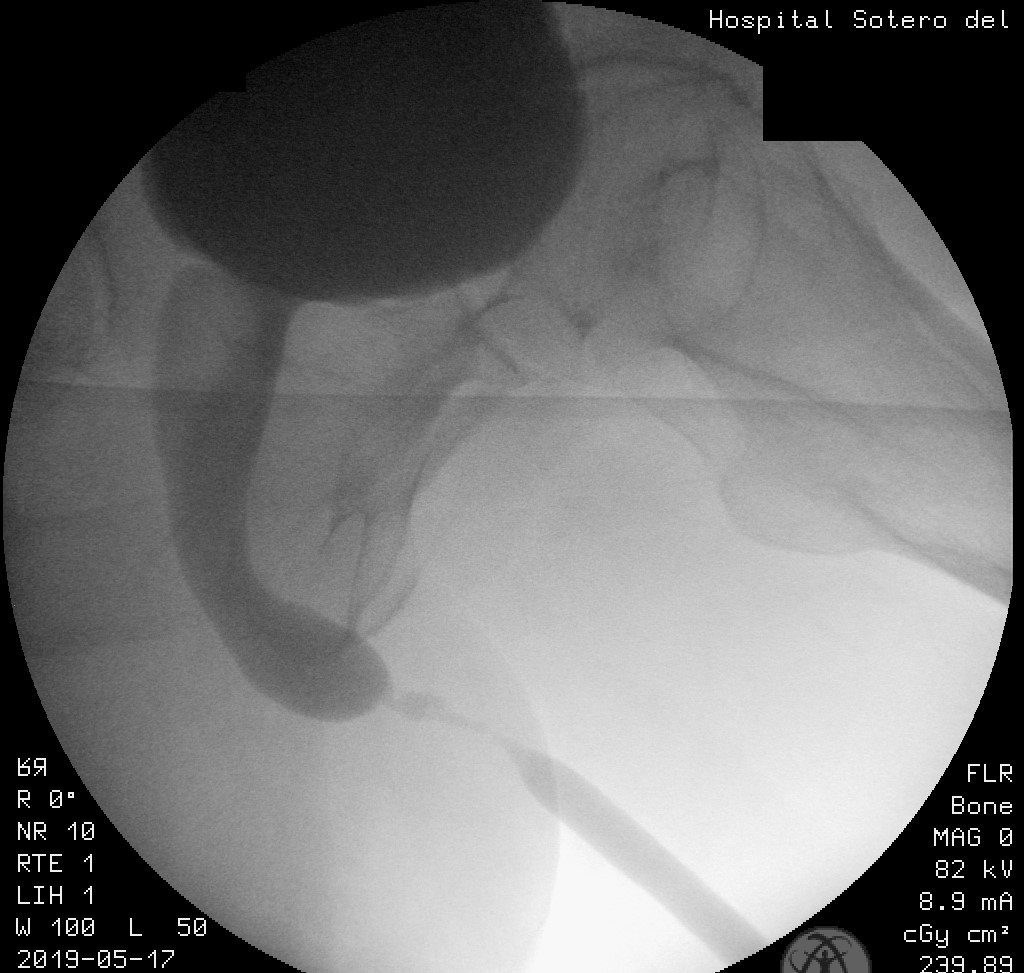

- La uretrocistografía retrógrada/miccional (UCG), es un examen dinámico que se realiza mediante la instilación uretral de contraste hidrosoluble bajo fluoroscopía y se recomienda que siempre sea hecha por el urólogo entrenado.20 Es el examen de elección para etapificación de las E/E. La UCG se encarga de definir la longitud, ubicación, severidad y número de las E/E. Además, da información sobre fístulas, duplicación uretral, falsa vía y el status del cuello vesical. El estudio completo consta de 2 fases: la fase retrógrada dibuja la uretra anterior y la fase miccional dibuja la uretra posterior, no siendo intercambiables, como se muestra en las imágenes. La fase retrógrada debe realizarse con el paciente en decúbito lateral con inclinación de 45°, permitiendo ver un orificio obturador “ocluido” en la imagen; con la cadera inferior flectada igualmente en 45° y la cadera superior extendida, y con el pene en estiramiento. (Fig 5). La fase miccional debe hacerse con la mesa en posición vertical y el paciente con deseo miccional, haciendo el registro en forma continua. (Fig. 6).

| Figura 6. Uretrocistografía en fase miccional. Se aprecia el cuello, la uretra prostática, la uretra membranosa y la bulbar proximal abiertas, mientras se evidencia una estrechez crítica de la uretra bulbar media, con dilatación proximal a la estrechez. |